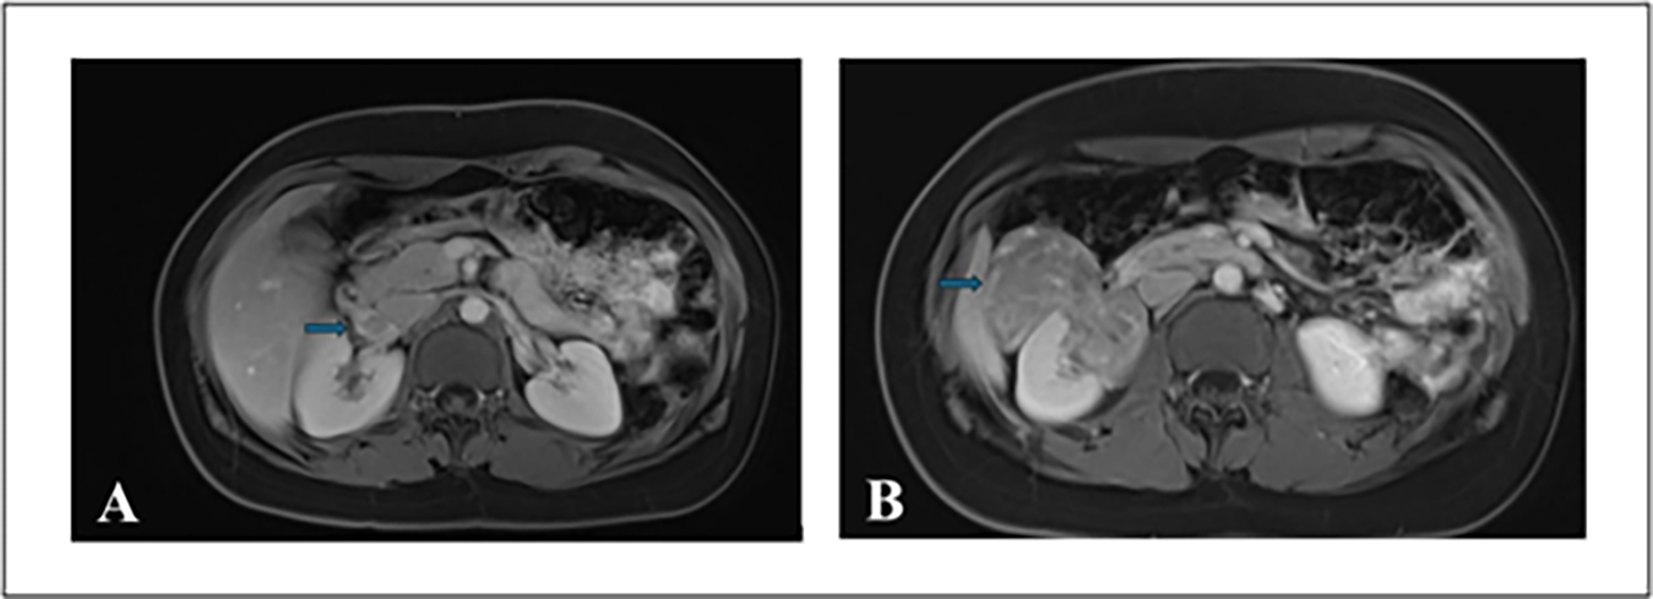

A contrast-enhanced computed tomography (CT) scan of the abdomen and pelvis demonstrated a heterogenous 11.5 cm partially enhancing mass at the right lower pole of the kidney with mild right hydronephrosis. Follow-up magnetic resonance imaging (MRI) performed two weeks later revealed a solid 11.9 cm exophytic mid/lower pole renal mass with evidence of tumor thrombus extending into the right renal vein and the infrahepatic portion of the IVC (Figure 1). Heterogeneous nodular enhancement with hypointense T2 signal suggested RCC. There was no evidence of lymphadenopathy or pulmonary metastases on imaging. The physical examination and metabolic workup were unremarkable.

FIGURE 1. Multiplanar multi-sequence MRI of abdomen and pelvis with gadolinium enhancement. (A) Axial image showing a right renal mass with the arrow indicating tumor thrombus in the right renal vein. (B) Axial image with the arrow demonstrating an exophytic mass in the right kidney